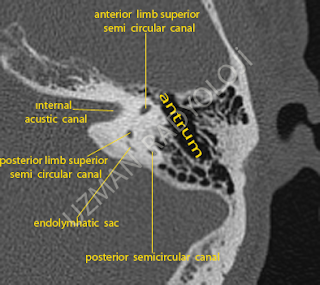

Semisirküler kanallar (canales semicirculares): Bu kanallar (anterior,posterior ve lateral ) vestubulum'un kemik labirenti ile ilişkilidir. Vestibulum' un arka-üst' üne doğru uzanırlar ve vestibulum içine açılırlar. Bunlar birbirine dik açı yapacak şekilde ve üç boyutlu bir şekilde yerleşmiştir. Her iki semisirküler kanal, bir dairenin 2/3'ü kadardır ve sondaki bir tanesinde bulunan ampulla hariç çapları 1.5 mm'dir.

posterior semicircular canal.

Endolymphatic sac: Duktus endolenfatius kemik labirentin aquaductus vestibulisini çapraz olarak geçer, fossakranii posteriorun kemik kısmına doğru devam eder ve burada kör bir keseye yayılır. Bu kesenin adı saccus endolymphaticus (sakkus endolenfatikus) tur. Bu kese temporal kemiğin pars petrozasının arka bölümünde duramaterin altında yer alır.

A: Mastoid antrum: temporal kemiğin mastoid çıkıntısındaki bir boşluktur. Antrum kavitesi tympanik kavite benzeri tegmen timpani olarak adlandırılan ince kemiksi çatıyla fossa cranii media'dan ayrılır. Antrumun tabanı mastoid hücrelerle ilişki kuran birçok açıklığa sahiptir. Antrum ve mastoid hücreler, mukoz membranla çevrilidirler ve orta kulağın sınırıyla devam eder. Ön ve altta, mastoid antrum fasial kanal ile ilişkilidir.

Internal acustic canal: Temporal kemiğin pars petrozasının 1 cm içinde lateral olarak uzanan dar bir kanaldır. Bu kanalın açıldığı yer temporal kemiğin posterior medial parçasında olup, dış kulak yolu ile aynı düzlem içindedir. Bu kanalın lateral bölümü gerekli bir kemik parçası ile iç kulaktan ayrılmıştır.

Anterior limb superior semi circular canal ( süperior semisirküler kanalın anterior dudağı)

Posterior limb superior semi circular canal (süperior semisirküler kanalın posterior dudağı)

Anterior limb superior semi circular canal ( süperior semisirküler kanalın anterior dudağı)

Posterior limb superior semi circular canal (süperior semisirküler kanalın posterior dudağı)